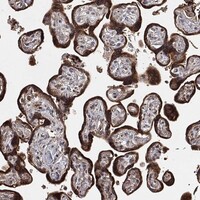

Enhanced - Orthogonal

Antibody staining mainly consistent with RNA expression data across 44 tissues.

HIGH EXPRESSION

Placenta

RNA expression: 63.5 nTPM

LOW EXPRESSION

Tonsil

RNA expression: 8.1 nTPM